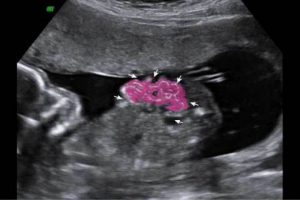

Diplomados en Ultrasonografía